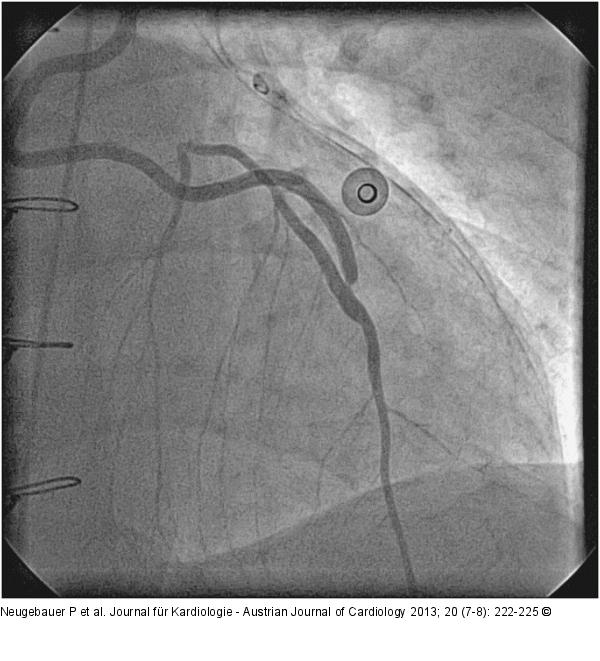

Abbildung 2: Catheter-Induced Dissection Angio of LIMA: 90% stenosis in LIMA-LAD anastomosis. |

Abbildung 2: Catheter-Induced Dissection

Angio of LIMA: 90% stenosis in LIMA-LAD anastomosis. |